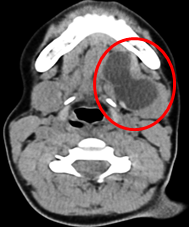

· Computed Tomography (CT): CT imaging can be used to evaluate the exact location and extent of the cyst, especially in cases where there is concern for deeper tissue involvement or compression of other structures. The cyst appears as a low-density, fluid-filled structure.